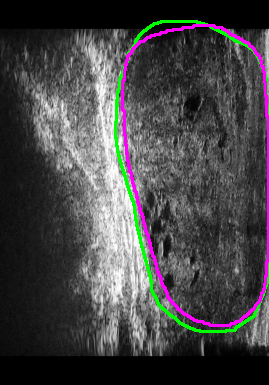

Figure 4 presents the performance evaluation of three loss functions—Adaptive Focal Loss, AG-BCE Loss, and PyTorch Focal Loss—on three test images. Each row in the figure corresponds to the segmentation results of one loss function, while the columns represent the respective test images. A legend at the top provides the color coding for the ground truth and the outputs of the three loss functions, allowing for a direct visual comparison of their performance.

The visual analysis of segmentation results, illustrated in Figure 5, demonstrates that Adaptive Focal Loss consistently achieves more accurate segmentation, particularly in regions with low contrast, high noise, or complex anatomical variations, closely aligning with the ground truth.

Further comparisons of Test 17, Test 18, and Test 19, shown in Figure 6, underscore the effectiveness of the Adaptive Focal Loss in handling challenging prostate boundary regions.

1.

Test Image 17: The Adaptive Focal Loss performed exceptionally well in the upper left region, which presented significant anatomical deformation, making segmentation particularly difficult. In contrast, AG-BCE produced an overly smooth boundary, while PyTorch Focal Loss severely under-segmented the area.

-

2.

Test Image 18: This image highlighted challenges in the lower prostate boundary caused by artifacts and low contrast. The Adaptive Focal Loss accurately delineated the boundary, whereas AG-BCE exhibited boundary shifts and PyTorch Focal Loss resulted in under-segmentation.

3.

Test Image 19: The Adaptive Focal Loss again outperformed the other methods, especially in the upper right region, where tissue density variations blurred the boundary. AG-BCE over-segmented this region, and PyTorch Focal Loss produced inconsistent results, with instances of both under- and over-segmentation.